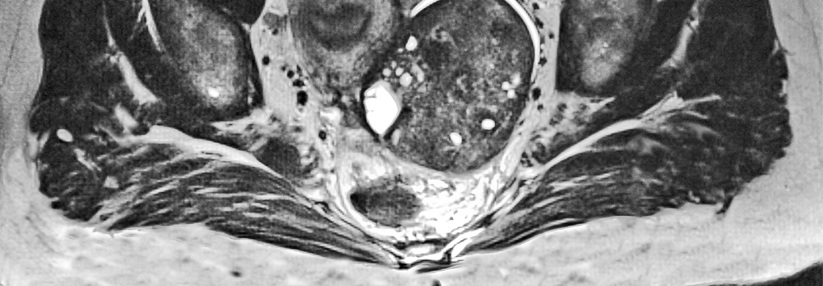

Erfolgreiche R0-Resektionen sind insbesondere beim Ovarialkarzinom von entscheidender prognostischer Bedeutung.

Erfolgreiche R0-Resektionen sind insbesondere beim Ovarialkarzinom von entscheidender prognostischer Bedeutung. © iStock/Raycat